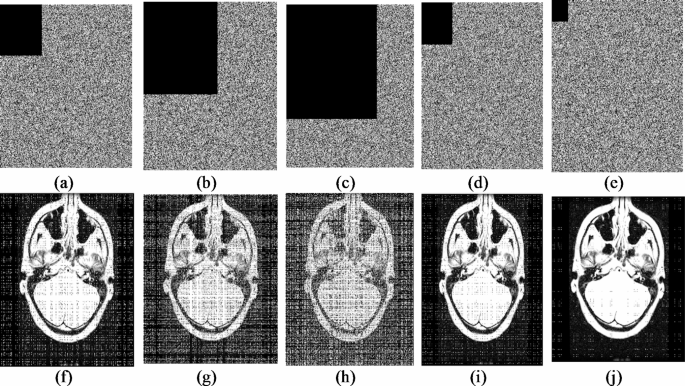

A cropping attack analysis is carried out to analyse the efficiency of the proposed encryption algorithm against intentional/unintentional data loss. In this analysis, the part of the cipher image is intentionally cropped, and the cropped cipher image is sent to the decryption module to retrieve the deciphered image. Cropping attack analysis is carried out for 10% (81 × 81), 30% (140 × 140), 50% (181 × 181), 64 × 64, 32 × 32 data loss as shown in Fig. 11. From Fig. 11, it can be seen that the decryption algorithm can get back the meaningful decrypted image with several data losses.

Cropping attack analysis: (a) 10% cropped cipher image (81 × 81), (b) 30% cropped cipher image (140 × 140), (c) 50% cropped cipher image (181 × 181), (d) Cropped cipher image of size 64 × 64, (e) Cropped cipher image 32 × 32, (f) Deciphered image of (a), (g) Deciphered image of (b), (h) Deciphered image of (c), (i) Deciphered image of (d), (j) Deciphered image of (e).